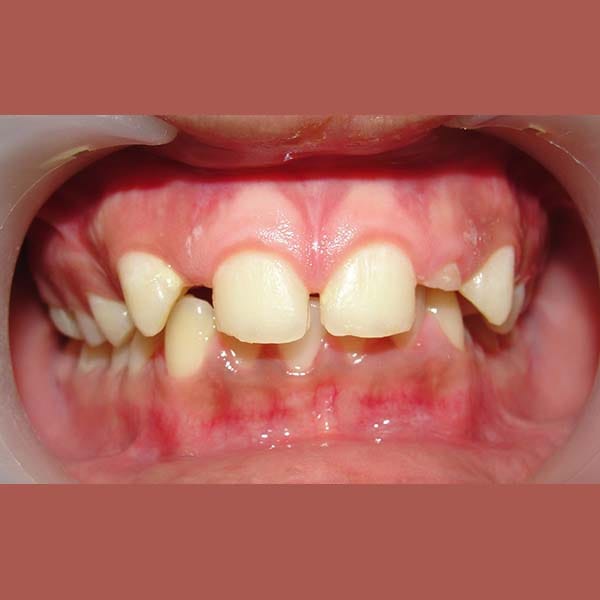

BEFORE

عانت هذه السيدة من وجود عضة عميقة أمامية و غياب خلقي لسنين أماميين سفليين ،بالإضافة لتراكب و عدم ارتصاف الأسنان الأمامية العلوية بشكل جيد – تم فتح مسافة كافية لوضع غرستين سنيتين و تم تصخيح العضة العميقة تقويمياً